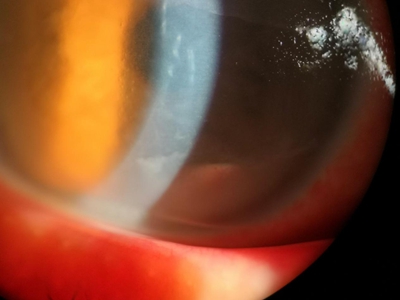

角膜挫伤角膜白色浑浊有血丝图

角膜挫伤眼睛的角膜有一大块黄绿色斑块,几乎覆盖整个眼球,除荧光绿色的斑块外,剩余角膜呈白色浑浊样,角膜下有部分红血丝,无法视物,病情较重。